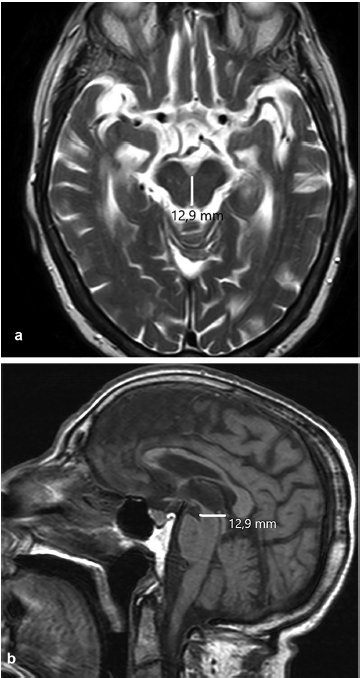

La RM es la modalidad de elección, prefiriéndose los cortes sagitales para la medición, ya que en los coronales se dificulta la visualización de los límites del agujero Magno.17

La medida debe tomarse trazando una línea recta entre el basión y el opistión del agujero Magno. Luego se traza una línea perpendicular a la primera, hasta el extremo distal de la amígdala herniada (►Fig. 3).

Existe disenso entre los estudios de cohorte en relación al valor exacto en milímetros del descenso amigdalar. La ►Tabla 1 resume las medidas del descenso amigdalar según el grupo etario.20

Existe relación entre el grado de descenso amigdalino y la presencia y grado de sintomatología,17 descensos menores a 10 mm suelen no dar síntomas.19